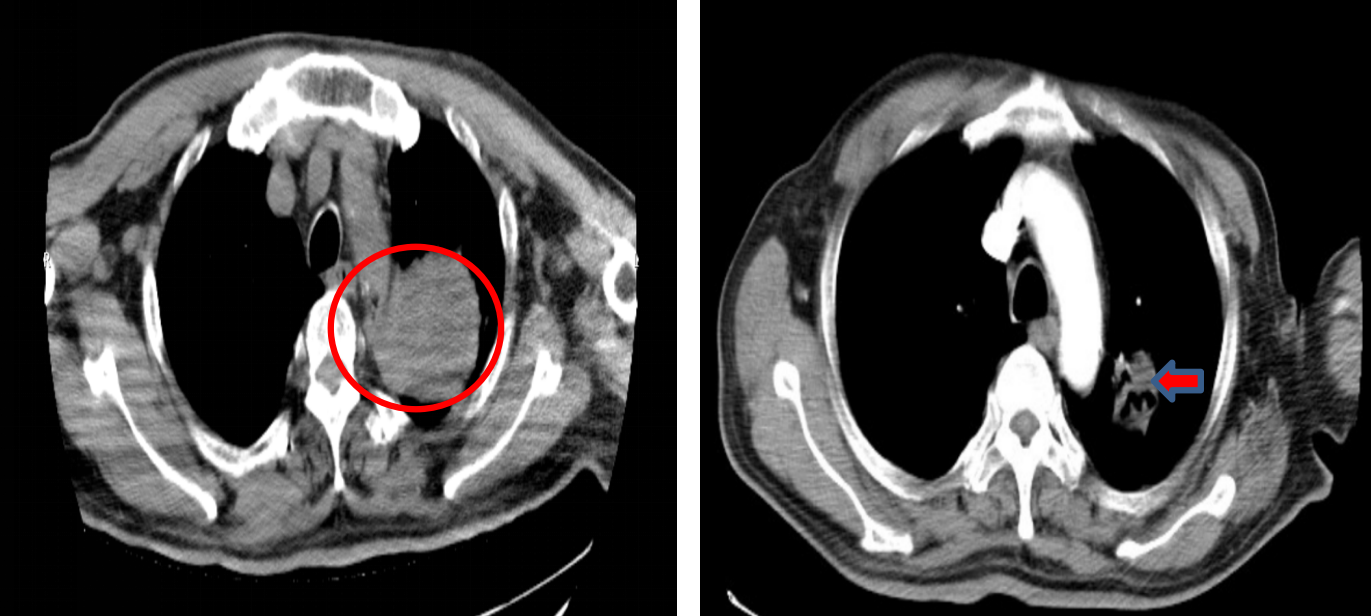

针对胸部病灶的进展,患者于2023年11月10日开始接受胸部姑息性放疗,放疗总剂量为:PTV 5500cGy,共25次,每次220cGy,放疗期间患者暂停用舒格利单抗。放疗结束后,于2024年1月29日继续重启舒格利单抗维持治疗。截至目前,患者已接受共计31个周期的舒格利单抗维持治疗,并仍在持续治疗中。

疗效评估

后续多次复查,胸部CT均提示病情维持稳定。

图片9.png

胸部CT(2023年11月-2025年3月)